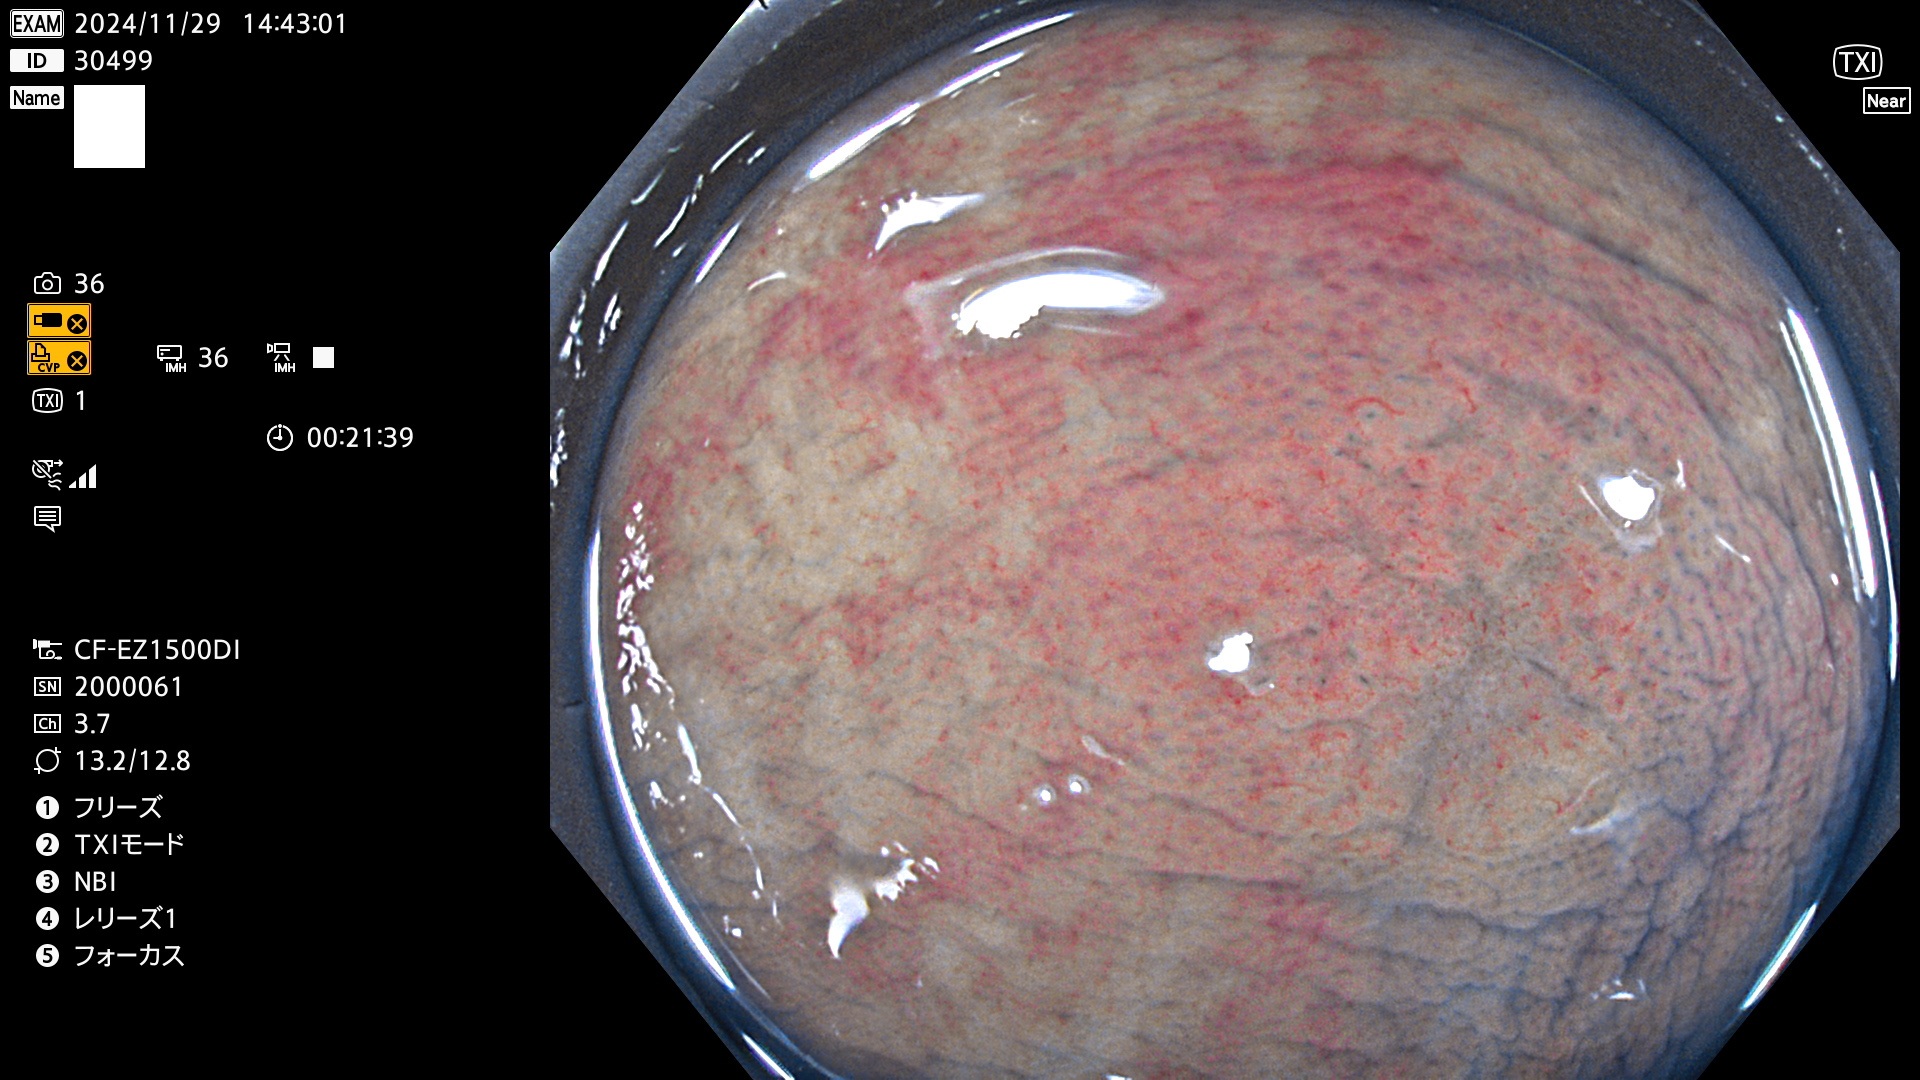

完全に平坦な物をUb、陥凹している物をUcと呼びます。最も発見が難しく危険な病変です。

毎週の検査(木・金・土・日)に発見されたUb、Uc型・腺腫を、その週の日曜の夜にUPし1週間、提示します。

抽出の対象期間 2024年11月28日〜12月2日の5日間(60件の検査)9件 (9/60=15%)